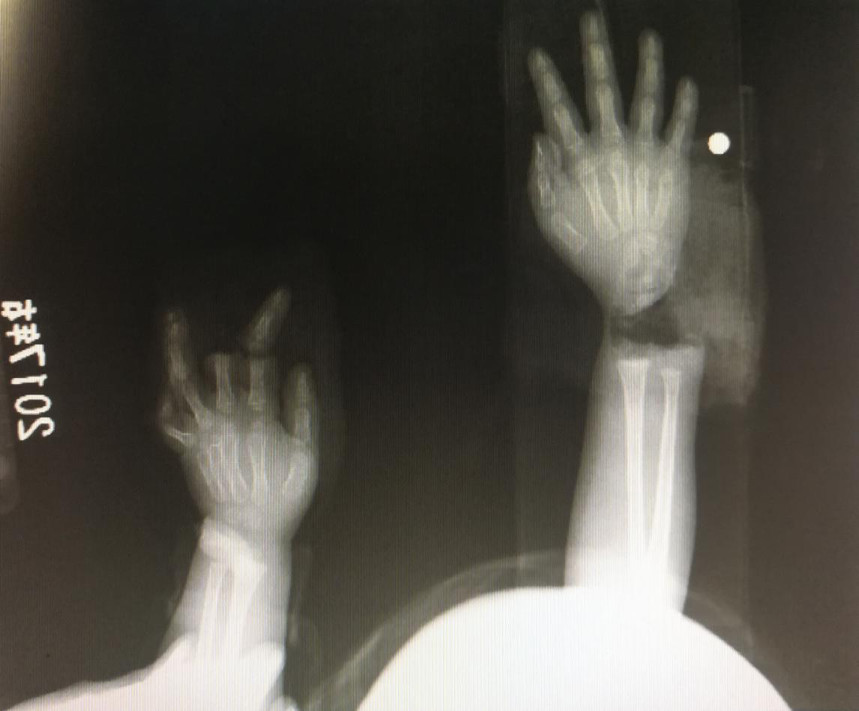

“急診在哪,急診在哪”,伴隨著一聲聲急促的問詢,一位年輕女士抱著渾身是血的小孩疾步前往急診室,懷里的小孩在疲憊與疼痛的交織下,時睡時醒。鑒于小孩的情況,急診醫(yī)生迅速安排給小孩拍了X光片,影像片結(jié)果顯示小孩左手手腕完全離斷,右手中、食指離斷,距離事發(fā)時間已經(jīng)3個多小時,需盡快安排手術(shù)。

經(jīng)過長達5個多小時的手術(shù),小宇(化名)終于被送出了手術(shù)室,離斷的手腕和手指均已完成再植,但關(guān)于斷指的存活與否還需要經(jīng)過一個十天的觀察期。小宇的主治醫(yī)生是長沙年輪骨科醫(yī)院手足外科馬思成醫(yī)生,據(jù)馬醫(yī)生介紹,小宇受傷情況比較嚴重,失血過多,而且兩個手都存在完全離斷的情況,手術(shù)時安排了兩組醫(yī)生同時進行,整個手術(shù)過程比較順利,目前小宇還處于觀察期。